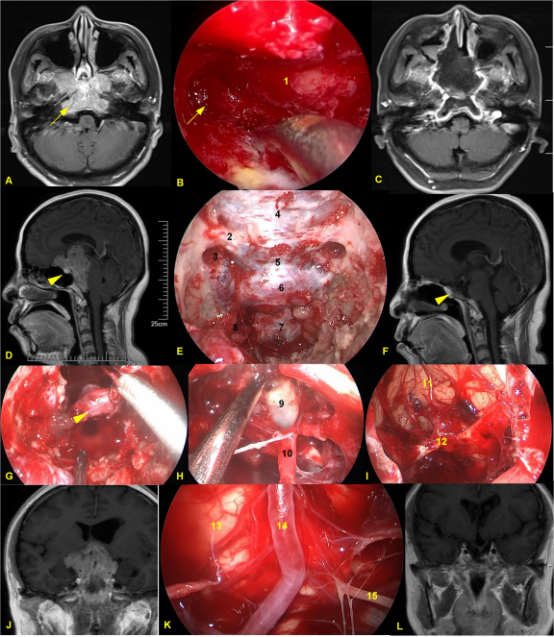

Figure 1. A-C,Pituitary adenoma with bone invasion. A. C preoperative and postoperative MRI. During the surgery, the bone of the jugular tubercle invaded by the tumor was removed. D-L Giant pituitary adenomas. D,F Pre-operation and 1 year post-operation MRI. E Intraoperative bone window exposure range. G.After tumor resection, the normal pituitary gland was preserved.H. After tumor resection, the third ventricle was opened. I The frontal lobe and Anterior communicating artery complex were exposed after tumor resection.K The brainstem and anterior pontine cistern were exposed. J,L. Pre-operation and 1 year post-operation MRI. 1 clivus; 2 Right optic canal; 3 optic canal-internal carotid artery recess; 4. The dura of the planum sphenoidale; 5 Dura of tuberculum sellae; 6. Dura m of sellar floor; 7. Clivus dura; 8. Para-clival internal carotid artery; 9 Third ventricle; 10 Pituitary stalk; 11 frontal gyrus; 12 Anterior communicating artery complex; 13 Brainstem; 14 Basilar artery; 15 Left abducens nerve. The yellow arrow shows the jugular tubercle invaded by the tumor; The untailed yellow arrow shows the normal pituitary gland.